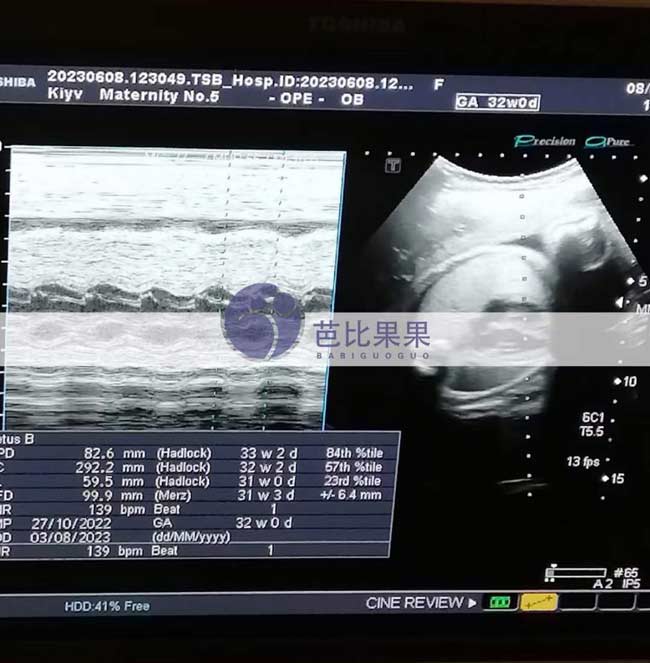

无锡W女士的乌克兰试管妈妈到妇产医院做32周的B超检查

无锡W女士的乌克兰试管妈妈到妇产医院做32周的B超检查,宝宝已经长得蛮大,离预产期越来越近,期待他的到来~